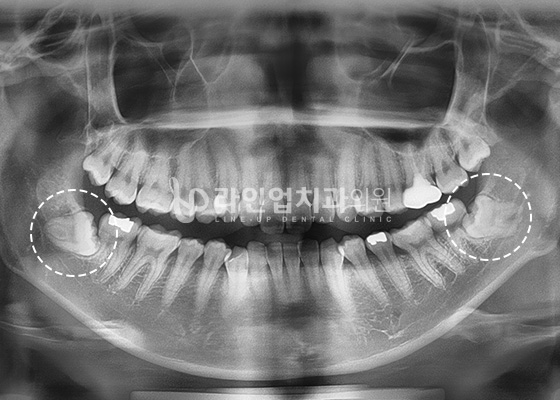

智齿拔除案例

Before